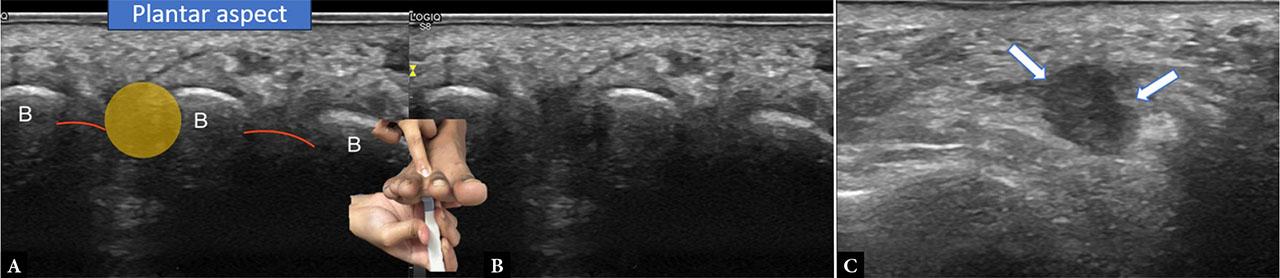

The intermetatarsal nerves, commonly discussed in the context of Morton’s neuroma, are another group of small peripheral nerves best evaluated with high-resolution sonography. These nerves course along the plantar aspect of the forefoot, between the meta-tarsal heads, superficial to the interosseous muscles and deep to the transverse metatarsal ligament(25). In healthy individuals, they appear as thin, hypoechoic, fascicular structures; however, when thickened or compressed, they may form fusiform enlargements classically described as Morton’s neuroma. Ultrasound has been shown to be highly sensitive in identifying these neuromas, with diagnostic accuracy comparable to MRI(26). A dynamic technique, applying forefoot compression, may accentuate bulging between the metatarsal heads. This is performed by placing the probe longitudinally in the intermetatarsal space on the plantar aspect and using a finger to compress the tissues from the dorsal aspect with an aim to accentuate bulging deep to the transverse metatarsal ligament(2). Ultrasound not only facilitates diagnosis but also guides therapeutic interventions such as corticosteroid or alcohol injections, allowing real-time confirmation of accurate perineural injectate placement(27) (Fig. 14).

Images A and B show an intermetatarsal neuroma (yellow) imaged from the plantar aspect with the probe placed transversely at the level of the metatarsal heads. The metatarsal heads (B) and the intermetatarsal ligament (red) can be seen. Finger pressure from the dorsal aspect accentuates the appearance of the neuroma by displacing it superficially. Image C shows the neuroma (between arrows) in the longitudinal plane